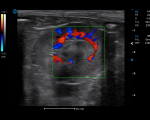

For Better Assessment Experience

CHI enhances the scattered echo and reduces the interference of tissue harmonics by contrast agents. The improved image resolution and sensitivity ease the recognition of lesion.

Strain Elastography differentiates tissue stiffness to distinguish mass and conventional tissue, effectively assisting the diagnosis of benign and malignant tumor.

Biopsy Guide & Needle Enhancement increase operation accuracy and efficiency with in-plane and out-of-plane biopsy guides, avoiding lengthy examination and inaccuracies caused by animal discomfort.